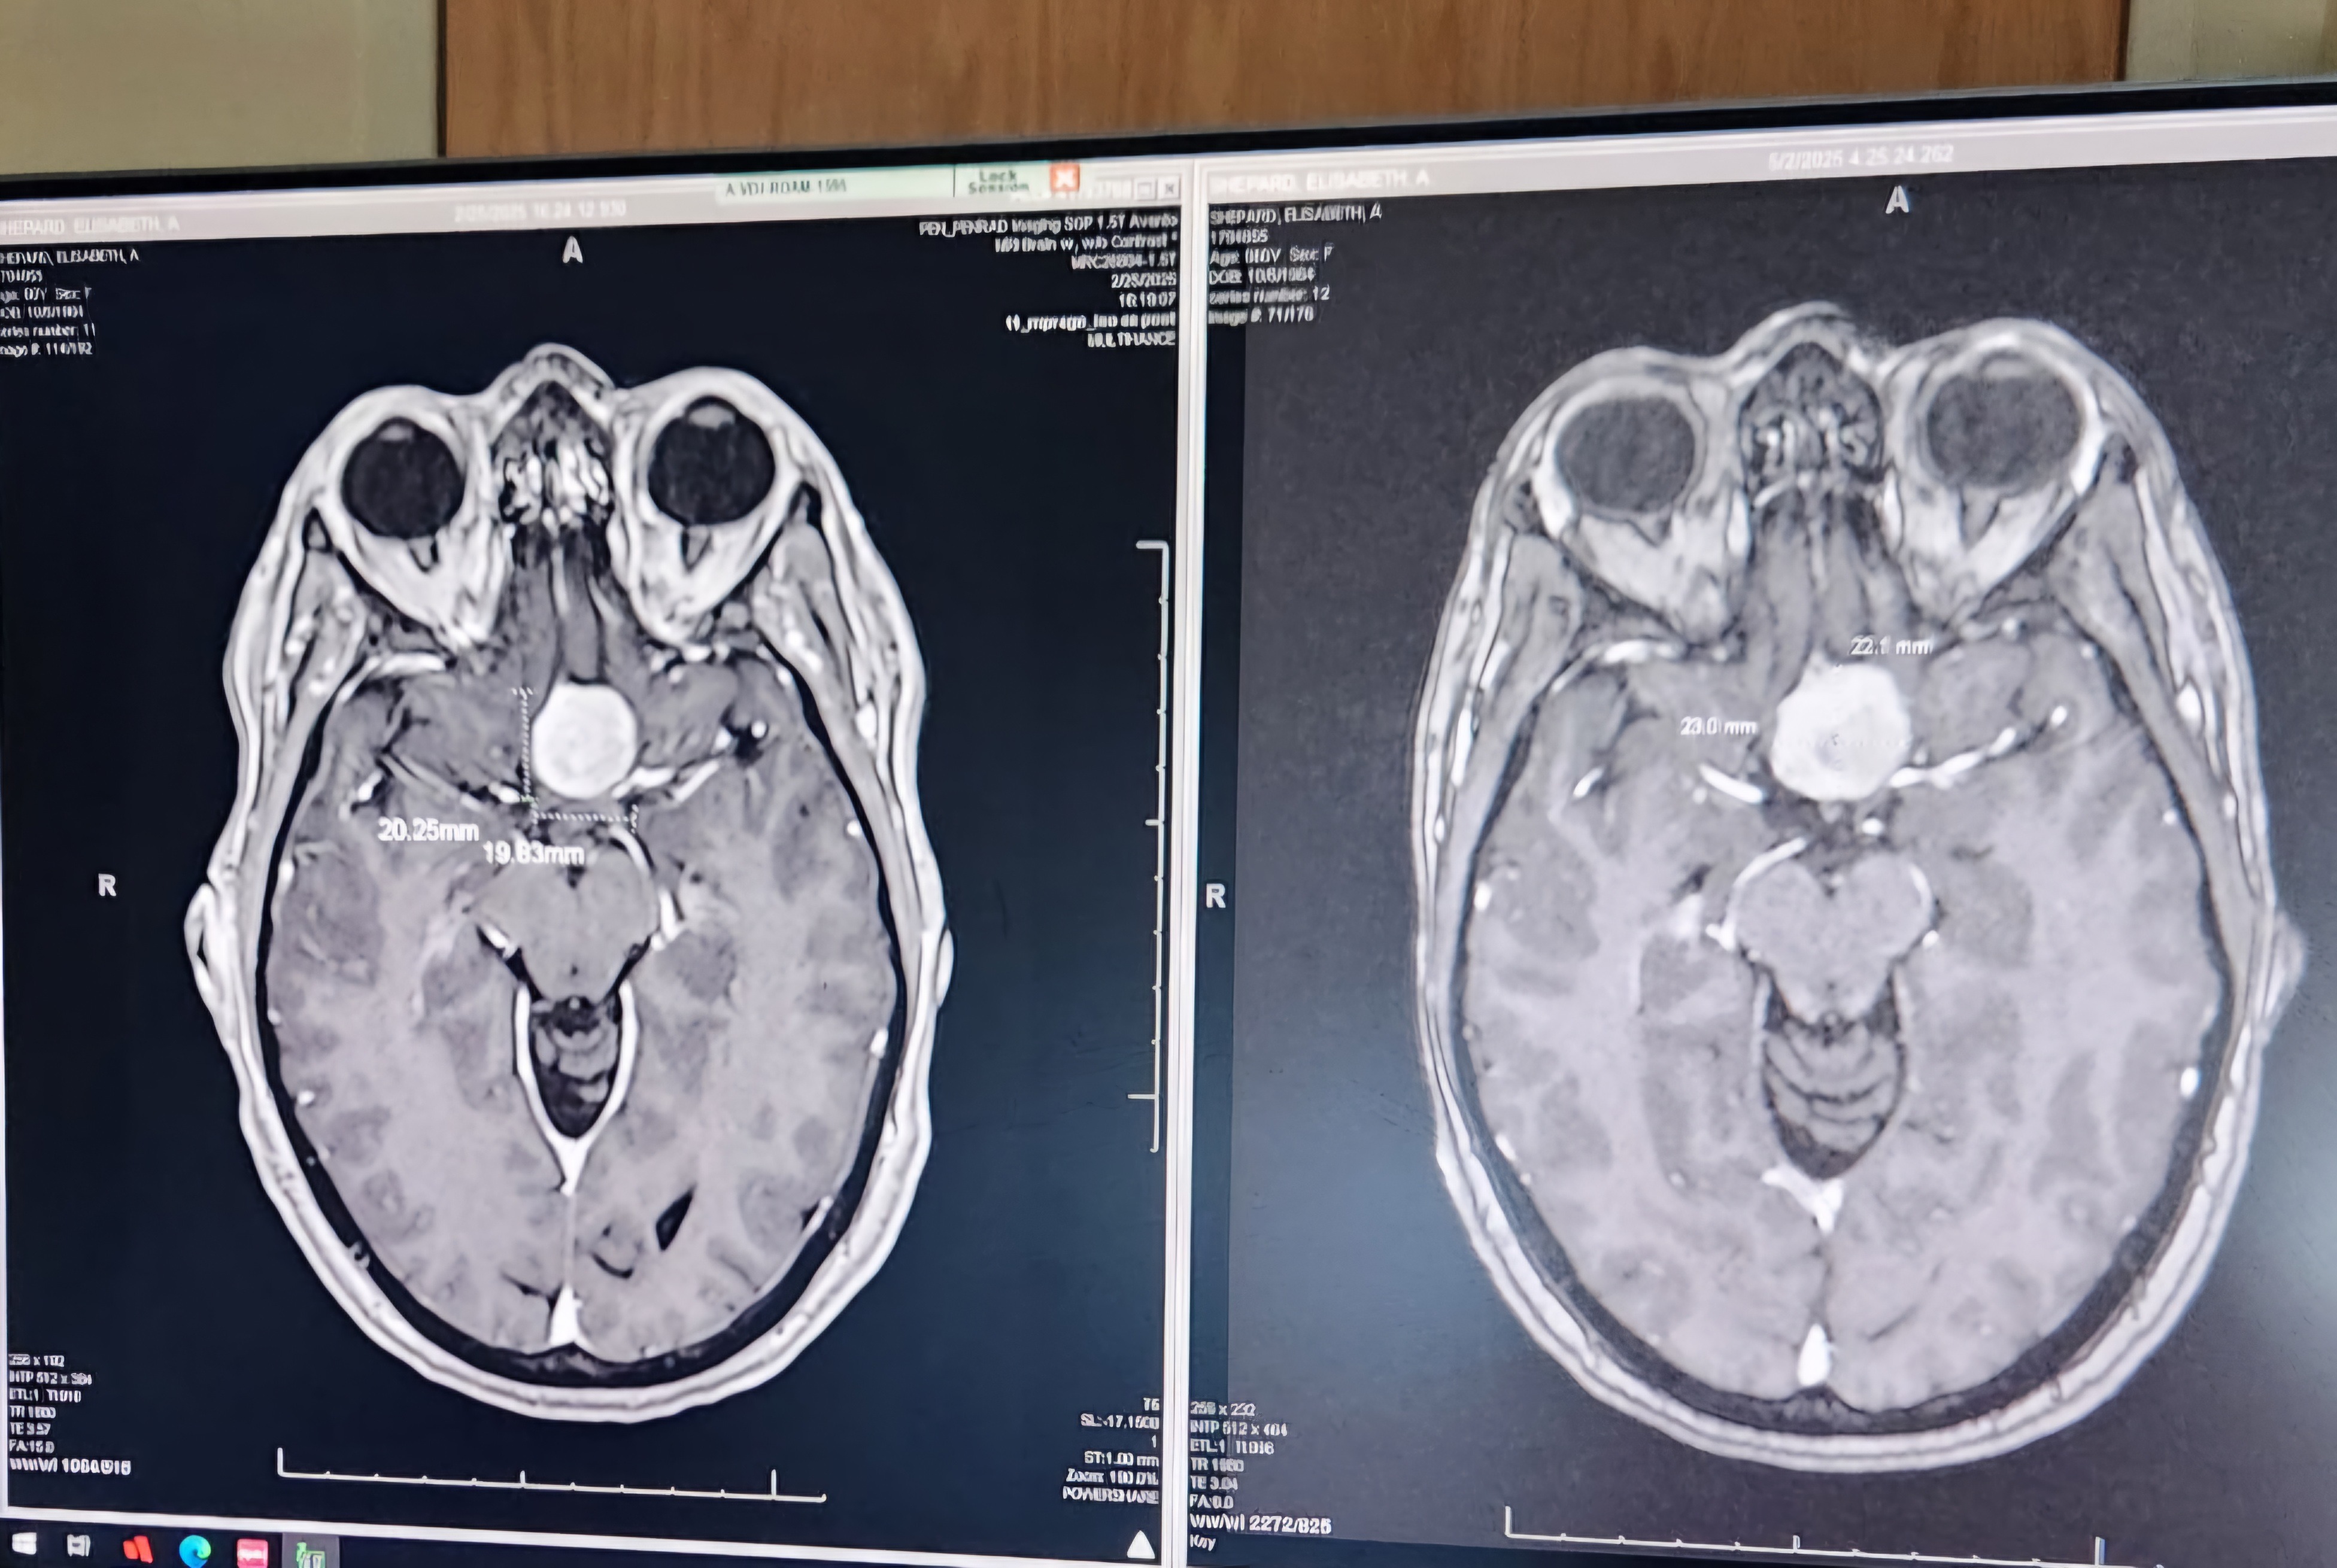

For those of you who don't know, Liz began experiencing vision difficulties at the end of 2023, steadily worsening until January 2025. The MRI on the left is from 2/2/25 and shows a 2cm by 2 cm mass compressing her optic nerve.

With the imminent fear that she would lose the vision in her right eye (already compromised), Liz's doctor arranged for her to be admitted to CU anschutz on 5/1/2025. The scans below were taken upon her admission and you can see that the tumor grew significantly in the 2 months since the scan on 2/25.